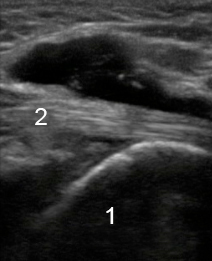

Bild: Sprunggelenk, medialer Erguss am Flexor hallucis longus, longitudinal

1. Longitudinal

2. Erguss am Flexor hallucis longus (FHL)